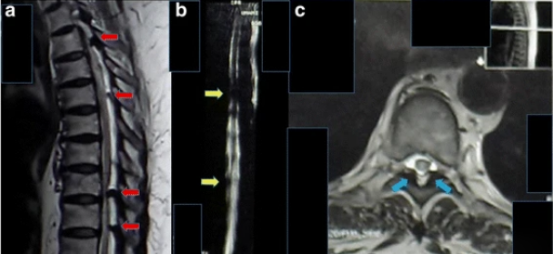

進行了胸部X光檢查,結(jié)果正常(見圖1)。T1加強磁共振成像顯示,Th8和Th9椎體后方硬膜內(nèi)位置有一個規(guī)律性的低強度病變,主要位于左側(cè)。該病變壓迫了脊髓向左。在T2加強磁共振成像中,病變相對于正常脊髓具有等強度(圖2)。

2 胸腔磁共振成像的矢狀面和軸向視圖,采用T1加強和T2加強圖像。a .T2加強磁共振成像的矢狀切片顯示,T3、T5、T8和T9等水平處多處脊髓受壓(紅色箭頭)。b . 磁共振成像-脊髓造影顯示T5和T9(黃色箭頭)水平處脊髓壓迫。c . T5椎骨水平的軸向視圖顯示左后部和右側(cè)的低強度腫塊(藍色箭頭)。